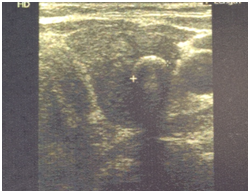

The patient was a 71 year old female with a history of autoimmune “Hashimoto” thyroiditis and hypothyroidism treated with 100mcg of L-Thyroxine per day. The rest of her personal as well as family history did not exhibit anything remarkable. The patient’s thyroid ultrasound showed a small heterogeneous thyroid gland consistent with chronic thyroiditis, and revealed a hypoechoic nodule on the upper left lobe 0.83 X 0.86 cm long with partially calcified capsule, irregular borders and vascularisation (Figure 1). The fine needle aspiration cytology of the nodule was inconclusive (the result came back as undiagnostic/undetermined). Since the patient had no family history suspicious for MTC and her serum calcitonin was 0.94 pg/ml (reference rate <4.6 pg/ml), there was no further investigation towards the diagnosis of MTC. She was advised for follow up and a new FNA of the suspicious nodule in six months. The patient however decided not to repeat the FNA, but instead to have a thyroidectomy. The pathology report came back as medullary thyroid carcinoma.